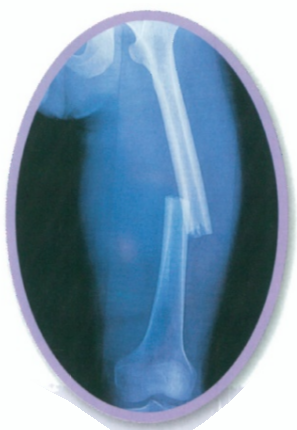

Sometimes we fall or have accidents and break our bones. A broken bone is called a fracture. Doctors take a special photo called an X-ray to see if a bone is broken or not. X-rays are photos that let us see inside our bodies.